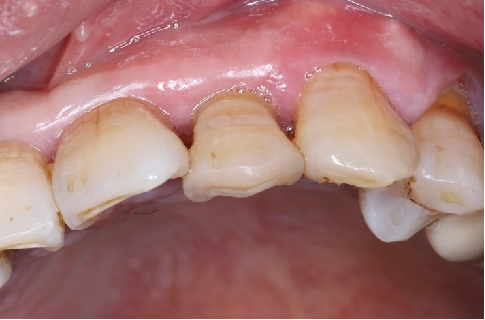

术后8周

牙龈软组织愈合,角化附着龈健康,口腔卫生一般,嘱患者重视日常口腔卫生维护。

术后4.5个月口内照片

术后4.5个月根尖片

ISQ动度值颊舌/近远中为70/73。